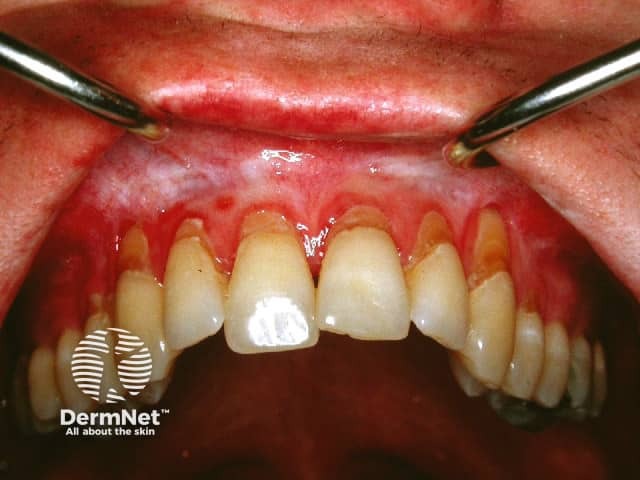

Atrophic/erosive lichen planus

Erosive pattern